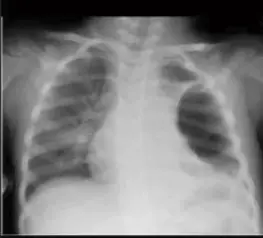

Pneumothorax

Case: Tension pneumothorax, Right Side

Findings:

- Midline shift

- Lung collapse

- Decreased air entry

Treatment: Needle decompression

Asthma with Pneumothorax / Emphysema (CXR)

in This PIC Be Curfiat → Check Countage of the lung

Hint: Loss of contour of lung

- Check if hyperinflated

The hint is loss of Couture of lung in the emphysema → we doubt see?

Scenario: 5 year old with 3 days of acute asthma, progressive SOB, cyanosis.

CXR findings?

- Right-sided pneumothorax OR emphysema with left mediastinal shift

- Loss of lung opacity

- Other mentions in original: “Liver & mucus”, “Pneumonitis”

Management?

- Bronchodilator, inhaled steroid

- Suction + physiotherapy

- If pneumothorax: chest tube — 5th intercostal space, anterior axillary line

- Possible intubation